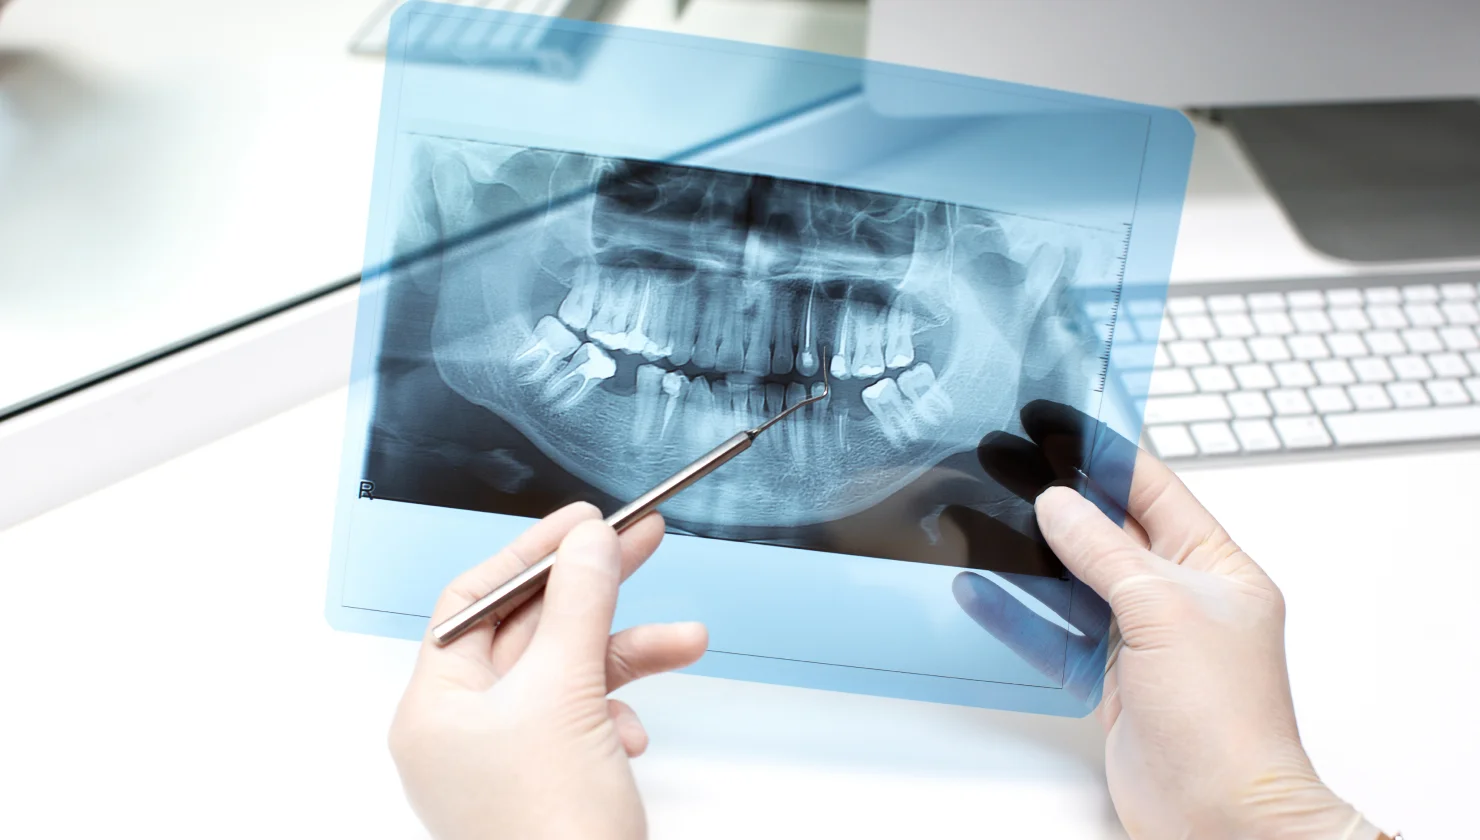

This fall, turn over a new leaf by investing in your smile with cosmetic dental treatments from Bloor West Smiles. Now is the perfect time to repair any cracks, chips, or discolouration left over from the summer months.

Fall Is the Perfect Time to Invest in a Cosmetic Dental Treatment

Popular Cosmetic Dentistry Procedures

Bloor West Smiles: Premier Cosmetic Dentistry in Toronto

Whether you’re looking to make a positive first impression at your new job or simply want to perfect your smile in time for the holidays, cosmetic treatments can help.

Cosmetic dentistry can help you step into the new season with confidence.